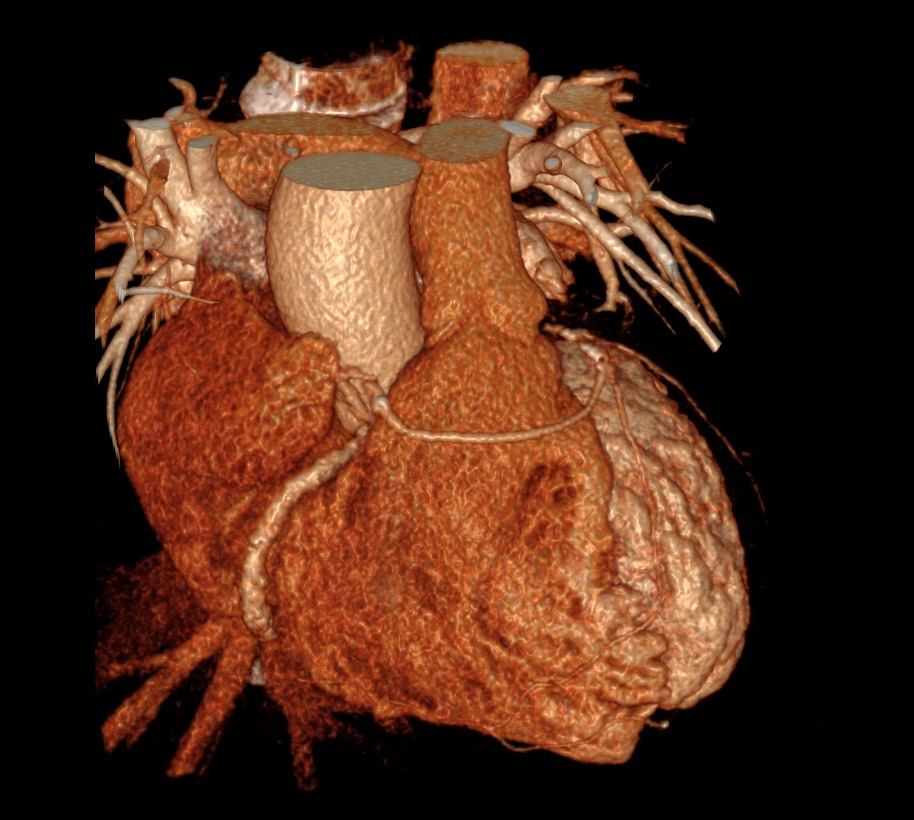

Cas

Coronaire Gauche

Coronaire droit

Depart CD et CG du sinus de valsalva droit, passant devant le tronc pulmonaire

Depart CD et CG du sinus de valsalva droit, passant devant le tronc pulmonaire

Trajet malin de la CD avec départ haut situé

Trajet malin de la CD avec départ haut situé